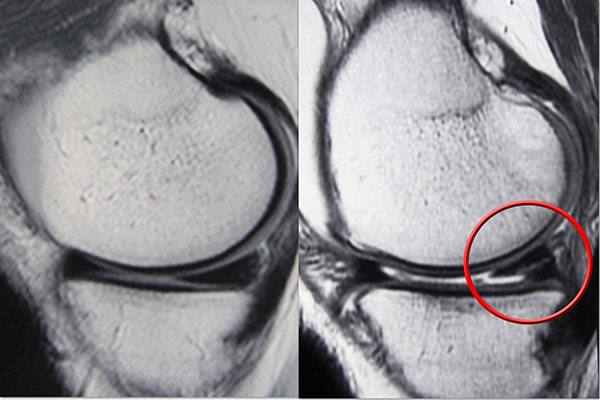

磁共振成像 (MRI) 掃描。 MRI 掃描可評估膝關(guān)節(jié)的軟組織,包括半月板、軟骨、肌腱和韌帶。